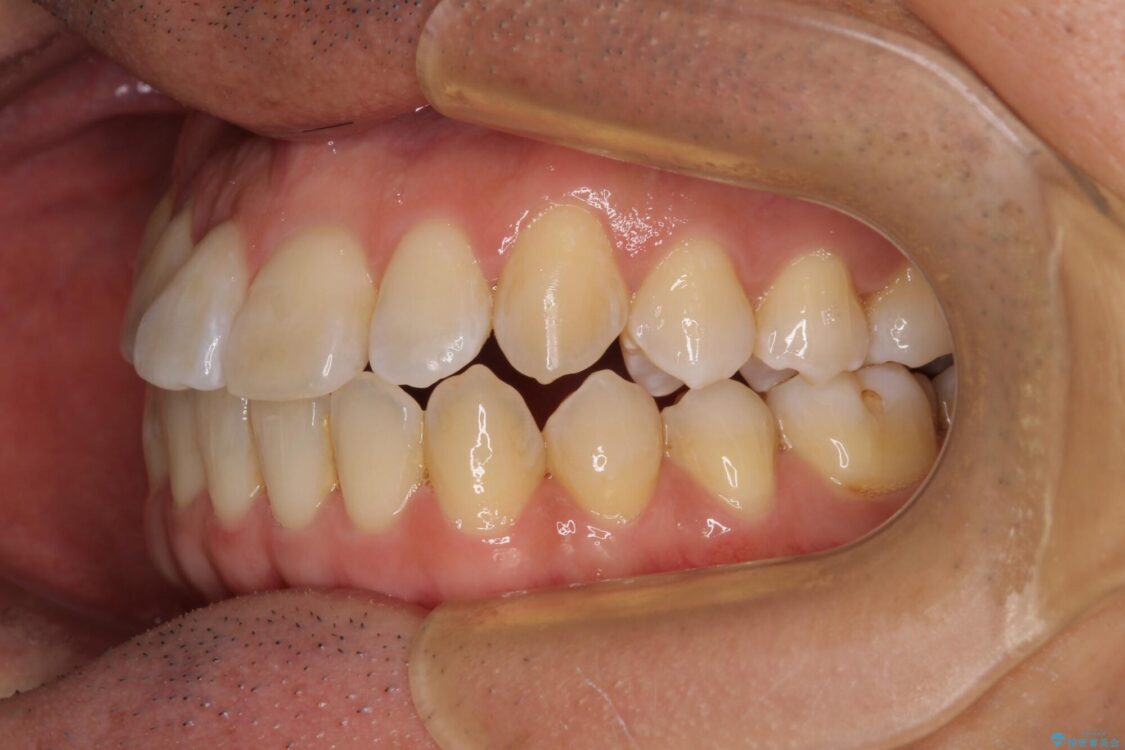

治療前

• 左右の八重歯が気になる ワイヤー装置での咬み合わせ改善 治療前画像